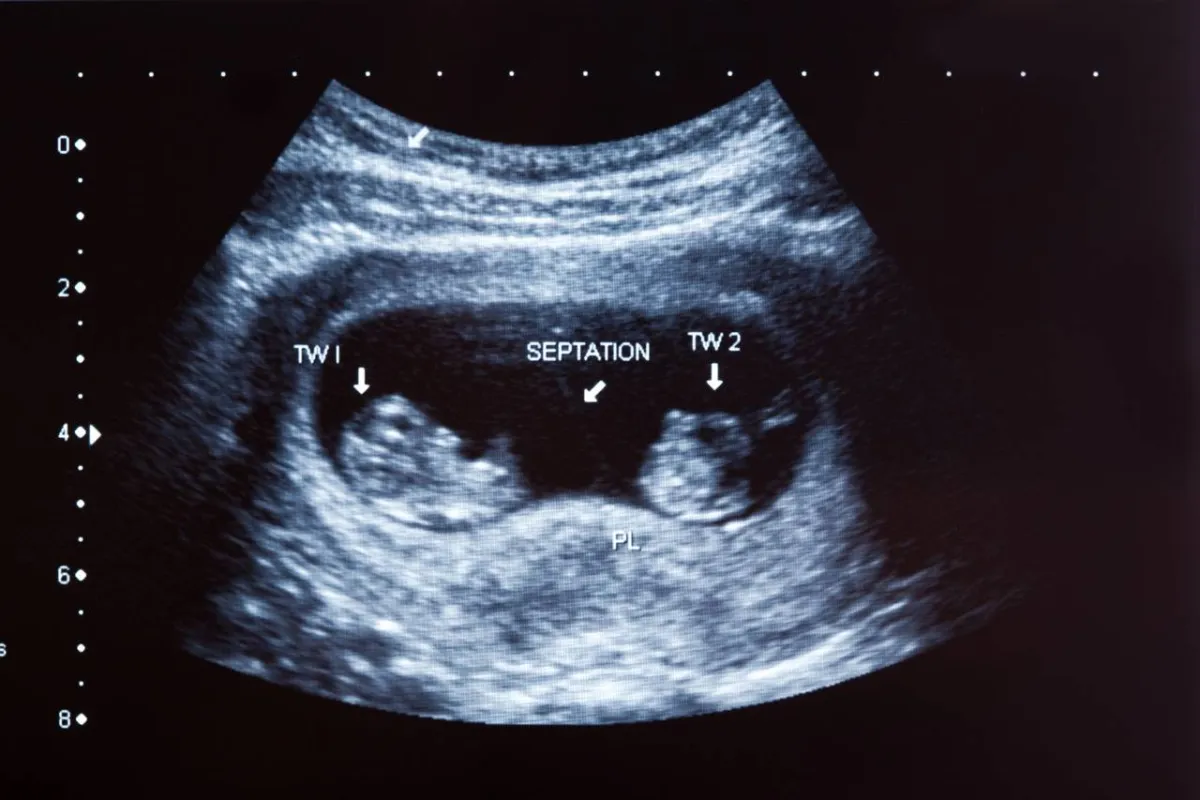

الحمل بتوأم، وتشوهات الجنين، أو وزن غير صحي للجنين.